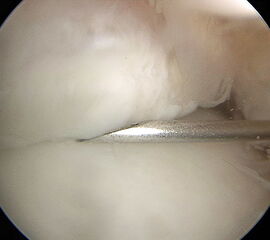

Abbildung 9, Video 4

Posttraumatische Arthrofibrose nach bimalleolärer OSG-Fraktur. Die ausgeprägten Verwachsungen (*) erschweren den Zugang zum Gelenk. Oftmals sind die intraartikulären Strukturen und der Gelenkspalt nach dem Einführen des Arthroskops nicht abgrenzbar, so dass zunächst eine Resektion der Narbenstränge mit einem Weichteilshaver erforderlich ist.